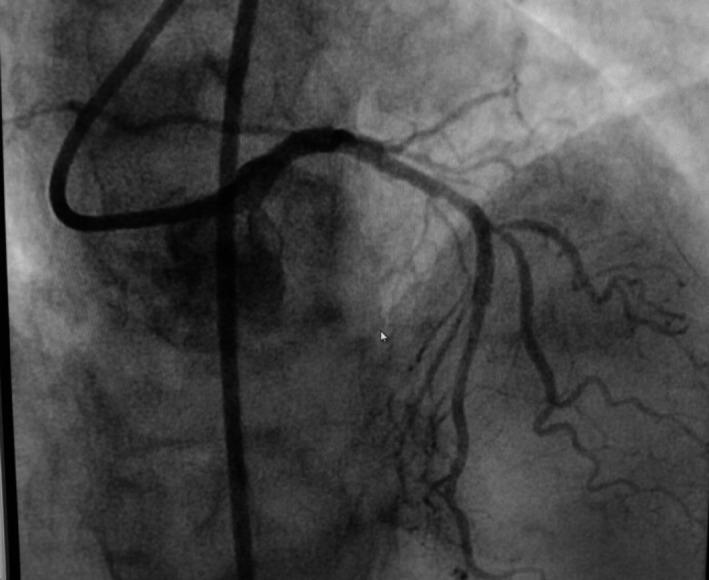

Possible links between inflammatory stimuli and atherothrombotic disease in the context of gallbladder pathology are not well understood. Our case demonstrates that clinical suspicion of cardiac disease after a diagnosis of acute cholecystitis should remain high in light of the dire consequences of a missed diagnosis.